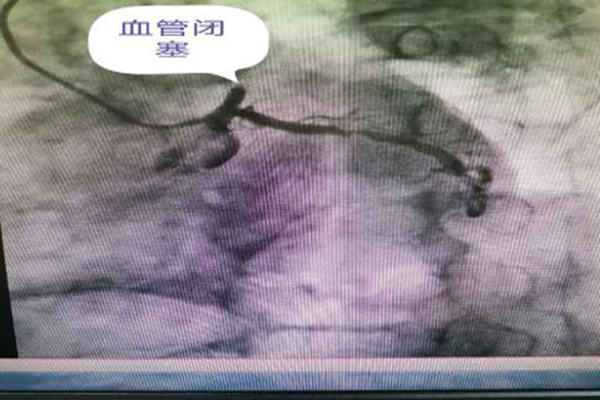

67歲的景大爺晚餐飽食后,突然感到持續(xù)胸痛、胸悶隨后出現(xiàn)全身大汗伴乏力,當(dāng)時(shí)家人都不在家,老人聯(lián)系家屬后,家屬及時(shí)撥打我院急救電話(huà),急救醫(yī)生到達(dá)后做心電圖檢查示急性廣泛前壁ST段抬高型心肌梗死。我院120醫(yī)生把患者的心電圖發(fā)入16醫(yī)院胸痛中心群內(nèi),一邊緊急救治一邊快速、明確地向景大爺家屬告知手術(shù)必要性及手術(shù)的高風(fēng)險(xiǎn)性,并迅速開(kāi)通胸痛中心綠色通道,通知導(dǎo)管介入手術(shù)室做好術(shù)前準(zhǔn)備。征得家屬的同意后立即將患者送入導(dǎo)管介入手術(shù)室行急診冠脈造影術(shù)。心內(nèi)科郭應(yīng)先主任及許慶華副主任立即冠脈造影示:左前降支近段閉塞,及時(shí)給于PTCA術(shù)治療,術(shù)后恢復(fù)2級(jí)血流,擇期行支架植入治療。心內(nèi)科郭應(yīng)先主任醫(yī)師說(shuō):“患者三支血管,一支完全閉塞,兩支次全閉塞,當(dāng)天我們?yōu)槠浯蛲?/span>罪犯血管——左前降支動(dòng)脈,待患者情況穩(wěn)定后,一周后擇期為其開(kāi)通右冠狀動(dòng)脈和左回旋支動(dòng)脈”。隨后,患者生命體征平穩(wěn),轉(zhuǎn)入了監(jiān)護(hù)病房。

血管閉塞

PTCA術(shù)后恢復(fù)血流